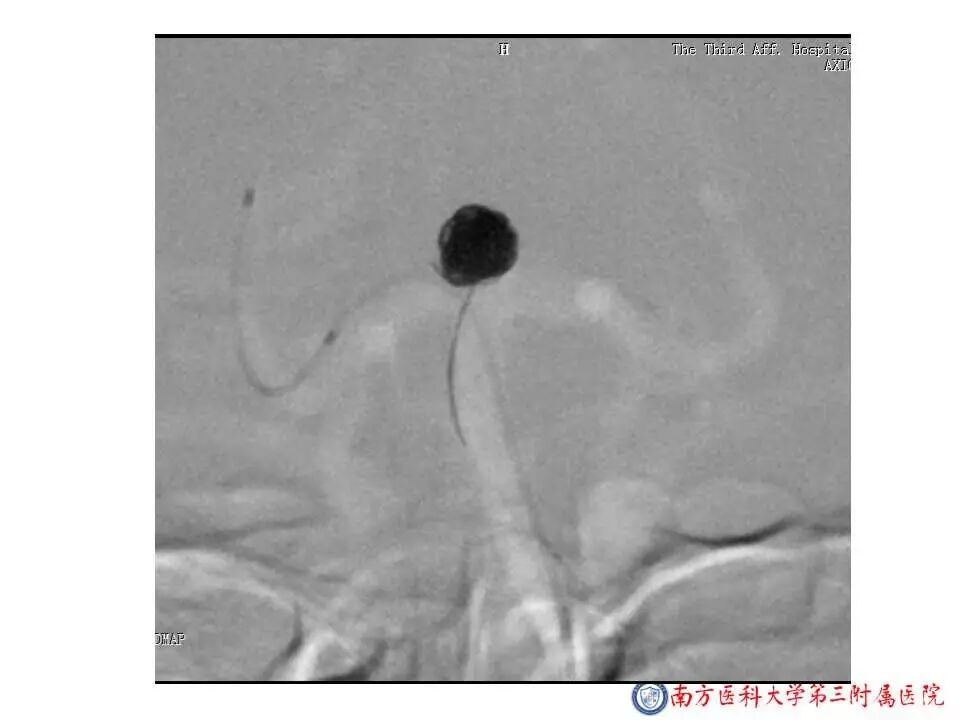

今天为大家分享的是“强生医疗CNV-神经介入专栏”第二十五期,由南方医科大学第三附属医院神经外科主任黄理金教授带来的“Enterprise支架辅助栓塞动脉瘤的优势”精彩讲课视频及PPT,欢迎观看。文章仅代表作者个人观点,如有不同见解,欢迎同道斧正!